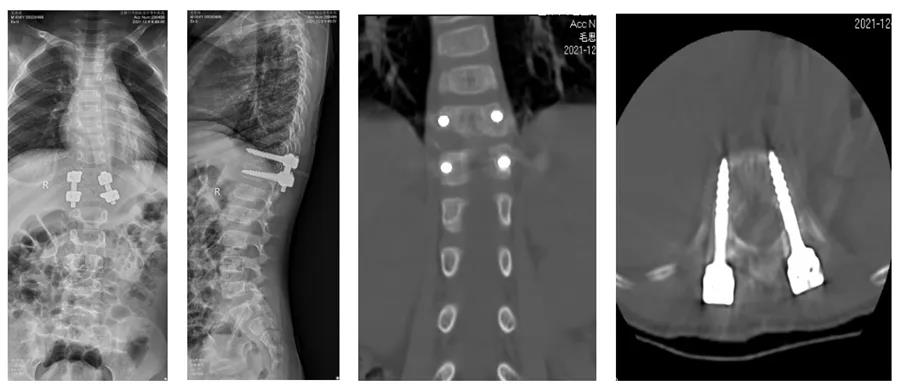

术前影像资料显示患儿胸11半椎体畸形

在脊柱二科陈涛主任的主持下讨论该患者的诊断及治疗方案,最后决定行胸11半椎体切除,钉棒上下短节段固定矫形。手术在陈涛主任及李嘉坤副主任带领下开展,手术中将胸11半椎体完全摘除,上下各用两枚椎弓根螺钉固定矫正侧弯畸形,手术历时2小时,出血约100ml,手术全程使用脊髓电生理监测,患儿手术全程监测运动、感觉电波正常。术后患儿双下肢肌力、感觉正常,复查影像学提示脊柱序列恢复正常,脊柱恢复“正直”。患者术后6天即可戴支具保护下床行走功能锻炼。

术后患儿影像资料,半椎体已完全切除,脊柱椎体序列恢复正常,脊柱恢复“正直”